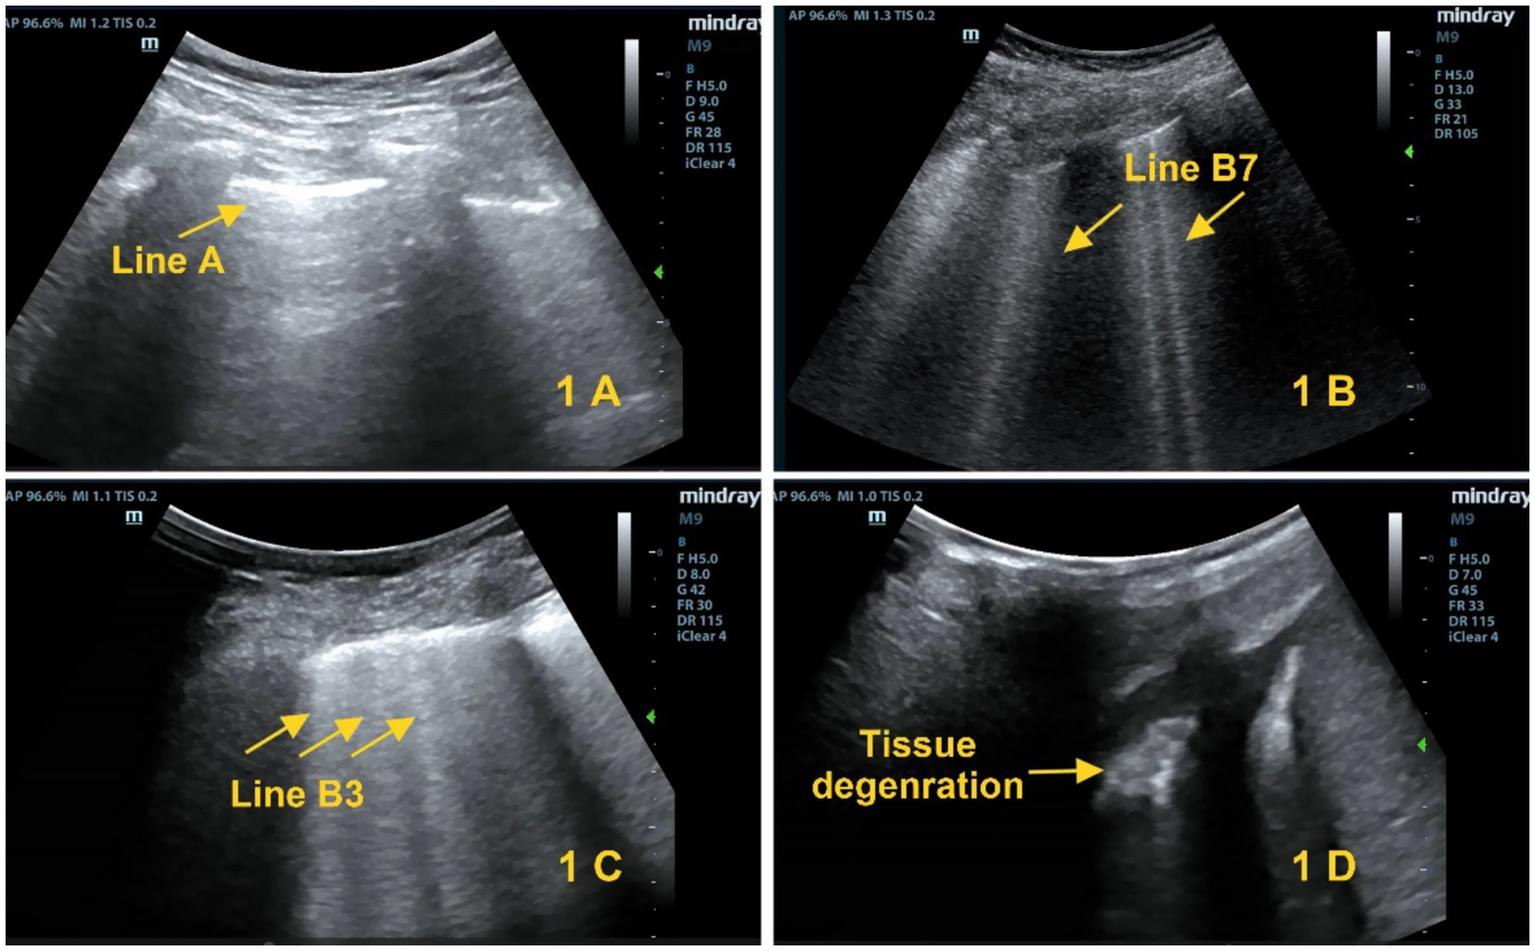

(1) Score 0: Pleural sliding sign with A-line visualization (Figure 1A); (2) Score 1: B7-line sign (B-line spacing of 7 mm, Figure 1B); (3) Score 2: B3-line sign (B-line spacing of 3 mm, Figure 1C); (4) Score 3: Shred sign/tissue-like change (Figure 1D). A 12-lung-zone (6 zones on each side) scanning method is used, and the total score ranges from 0 to 36 points (6).

Figure 1

Lung ultrasound scoring criteria. (A) Score 0: A-lines (yellow arrows). (B) Score 1: B1 lines (yellow arrows). (C) Score 2: B2 lines (yellow arrows). (D) Score 3: Tissue-like sign (yellow arrows).